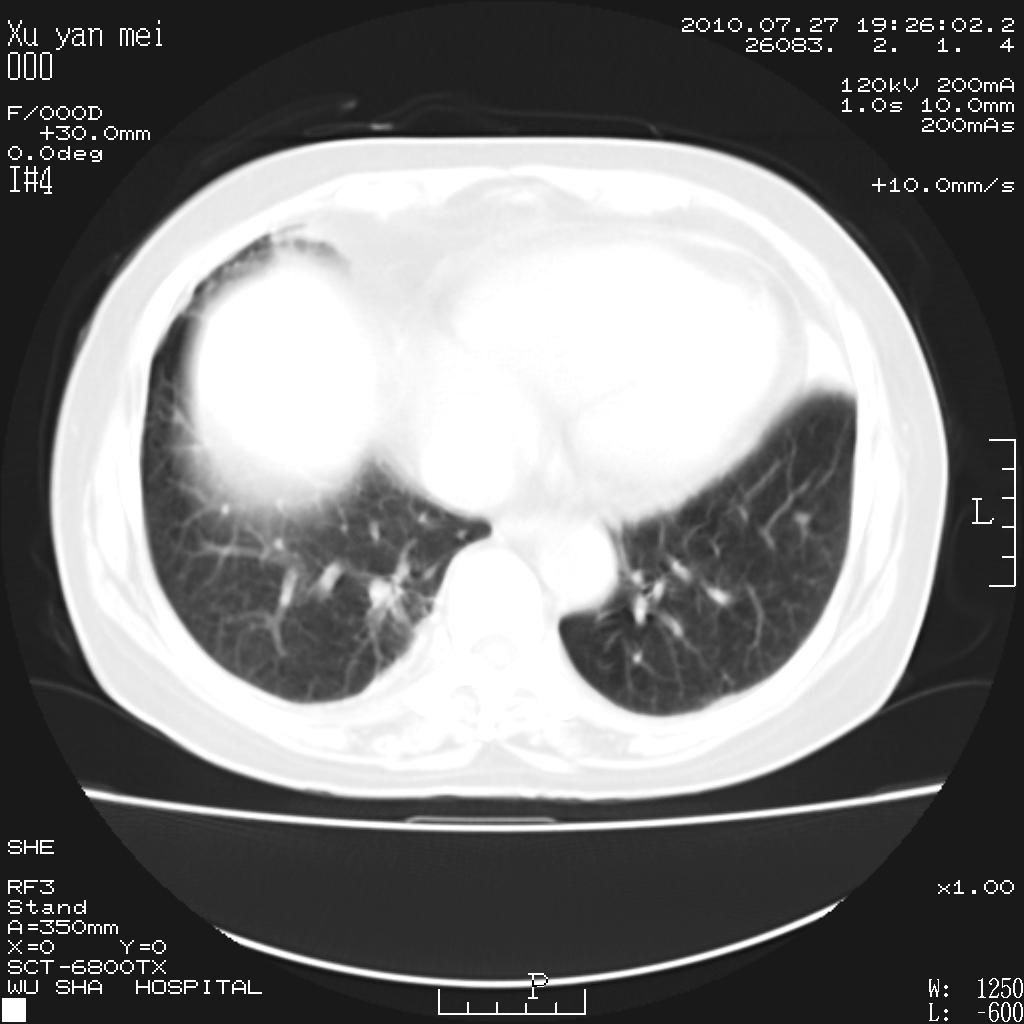

女,60岁,胸痛就诊,右肺结核?炎症?其它?(胸片右侧中上肺野确实看不到什么啊)

1)考虑两肺感染性病变;建议抗炎治疗后复查。2)双侧少量胸腔积液。

1)考虑两肺感染性病变;建议抗炎治疗后复查。2)右侧少量胸腔积液。

双肺炎症可能性大,建议抗炎后复查。右侧胸腔少量积液。双侧胸膜轻度增厚。

考虑两肺感染性病变;不除外肺栓;建议抗炎治疗后复查。